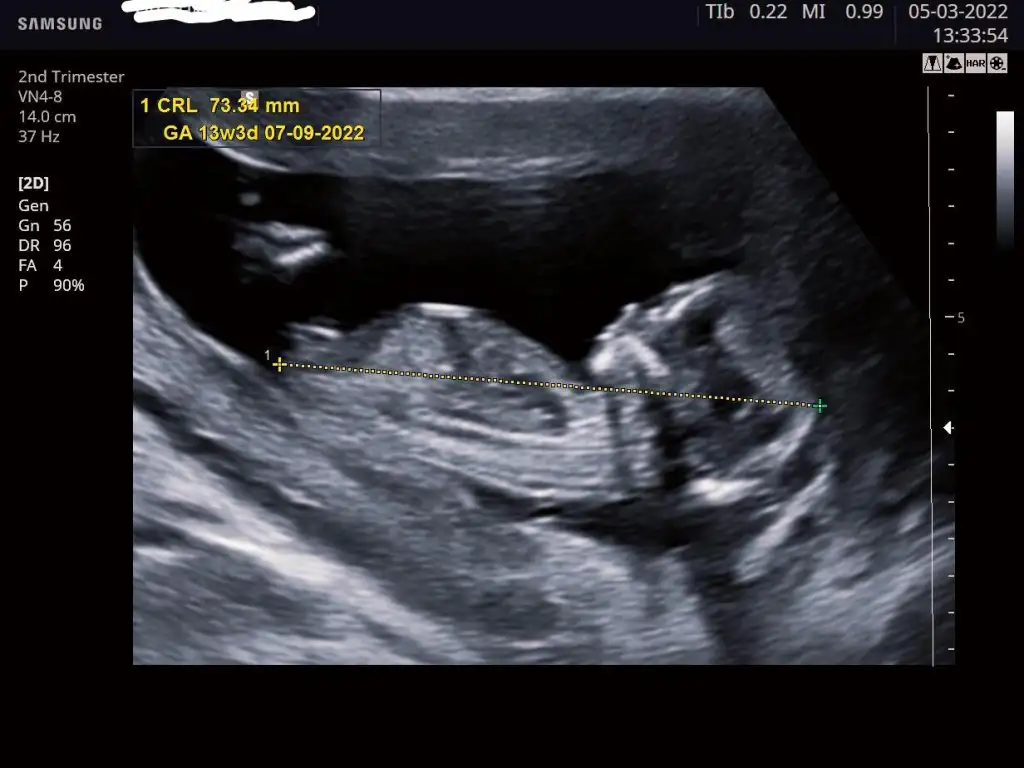

Geçen attığıma yorum yapmadınız anlaşılmıyordu sanırım 9 haftalıktı bu sefer büyümüş halini atıyorumAnlaşılır inşallah..

Burada 12+1 idiİkra meyra bir de sen bir tahminde bulun bakalım cinsiyetimize

Bi tahmin de biz alabilir miyizKız gibi